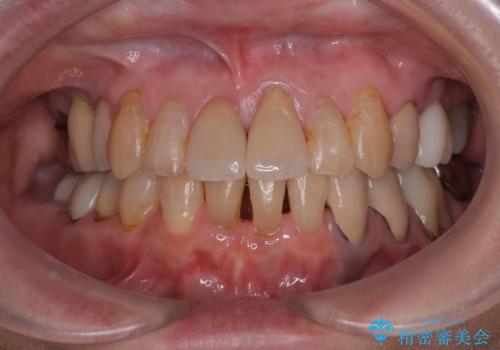

捻れて前に出ている前歯 ワイヤー装置での非抜歯矯正

長年気になっていた前歯 矯正治療と補綴治療による審美歯科治療

しみる前歯のセラミック治療 周辺も同時に治療して調和の取れた前歯に